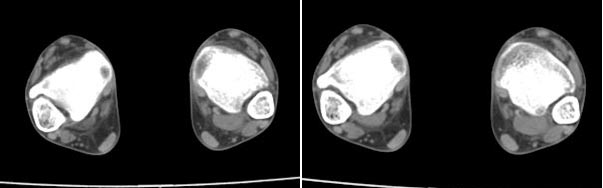

x线检查月前片示双踝关节骨质未见明显异常。一月后肿胀大部消失,疼痛稍有好转,摄片示两侧骨下段条带状高密度影,边界尚清。ct扫描示两侧胫骨下段骨皮质增厚不明显,髓腔内密度显示磨玻璃样增高,髓腔显示狭窄。

x线检查一个月前示双踝关节骨质未见异常。一个月后肿胀大部消失,疼痛稍有好转,摄片示两侧胫骨下段横行条状高密度影,边界较清。ct扫描示:两侧胫骨下段未见骨皮质增厚,两胫骨下段近骨端处可见骨小梁增粗但纹理尚清晰,未见明显骨质破坏,邻近关节及关节囊未见明显异常,软组织内未见异常.综上所诉考虑1.低毒感染所致,2.假性痛风

x线片表现为双侧胫骨下端粗条状磨玻璃样增高密度影,并可见骨皮质稍不连续。ct表现为双侧胫骨下端髓腔内磨玻璃样增高密度影,未见明显骨皮质不连续(可能与扫描体位有关)。

本例应该考虑为双侧胫骨下端应力性骨折。